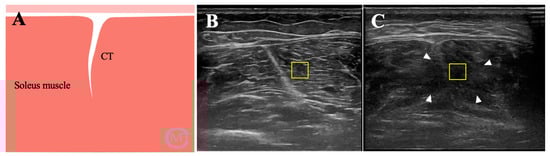

1. Introduction

2.7. Image Analysis